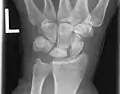

X-ray showing stage IIIB on right wrist, with ulnar impingement.